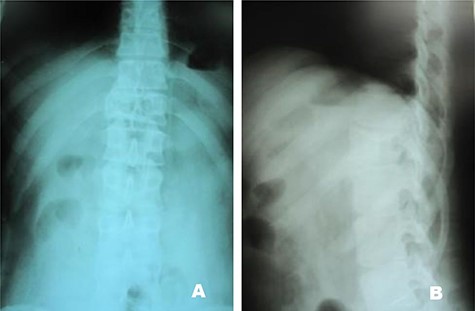

A 24-year-old male presented with acute low back pain with no prior traumatic events. Physical examination was unremarkable except for tenderness over the lower thoracic spine. The laboratory tests including complete blood count, renal function tests, alkaline phosphatase, aspartate aminotransferase, alanine aminotransferase, serum calcium, serum phosphorus and parathyroid hormone were all within normal limits. Initially, the patient was treated conservatively but the pain did not improve. Lumbar X-ray showed mild height loss and fracture of the superior endplate of T12 vertebra (Fig. 1). Computed tomography (CT) showed a multi-lobulated osteolytic lesion within the T12 body with extension to the right pedicle and transverse process (Fig. 2). Magnetic resonance imaging (MRI) revealed a well-defined lesion with low signal intensity on T1 and high signal intensity on T2 weighted images (Fig. 3). The bone scan showed a cold spot at the site of the lesion. The patient underwent surgery and excisional biopsy through the posterior approach. A large clear fluid-filled cavity was curetted and the cavity was filled with an autologous bone graft from iliac crest. Posterior spinal fusion was performed with instrumentation with pedicle screws from T10 to L2 and a mixture of autologous bone graft and allograft was used to achieve better fusion (Fig. 4). Pathology report confirmed the diagnosis of SBC and the patient received no further treatment (Fig. 5). The patient had no recurrence in 10-year follow up.

Case 1, (A): Anterior–posterior; (B): Lateral pre-operative X-ray.